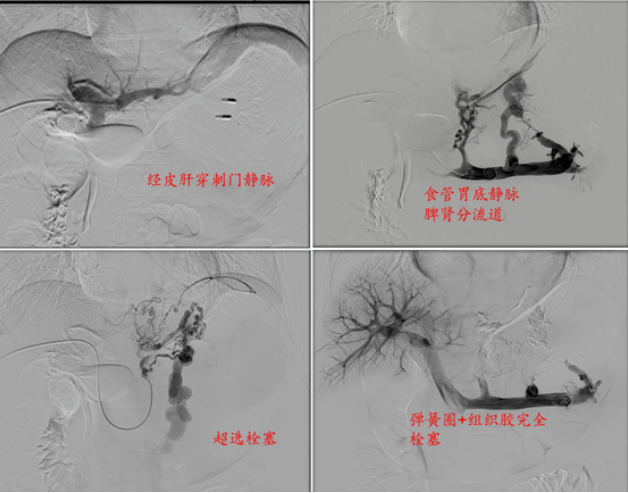

术中,刘一强快速精准采用一“堵”一“疏”的介入手术。1小时内完成止血,术后病情稳定,于第二天转回普通病房。

一“堵”:经皮肝穿食管胃底静脉栓塞, 快速止血稳定患者生命体征

一“疏”:经颈静脉肝内门体分流术(TIPS)或 经肠系膜上静脉肝外门体分流术(TEPS),建立人工分流道从根本上解决门静脉高压,为患者搭建生命通道!